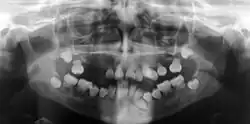

Preoperative panoramic radiographs showing features of dentin dysplasia type I

In other words, affected primary teeth usually have abnormal -shaped or shorter than normal roots. “Crescent/half-moon shaped” pulp chamber remnant in permanent teeth can be seen on x-rays. The roots may appear to be darker or radiolucent/pointy and short with apical constriction. Dentine is laid down abnormally and causes excessive growth within the pulp chamber. This will reduce the pulp space and eventually cause incomplete and total pulp chamber obliteration in permanent teeth.[12][13] Sometimes periapical pathology or cysts can be seen around the root apex.[11] Most cases of DD associated with peri-apical radiolucency/ pathology have been diagnosed as radicular cysts, but some of them have been as diagnosed peri-apical granuloma instead.[14]